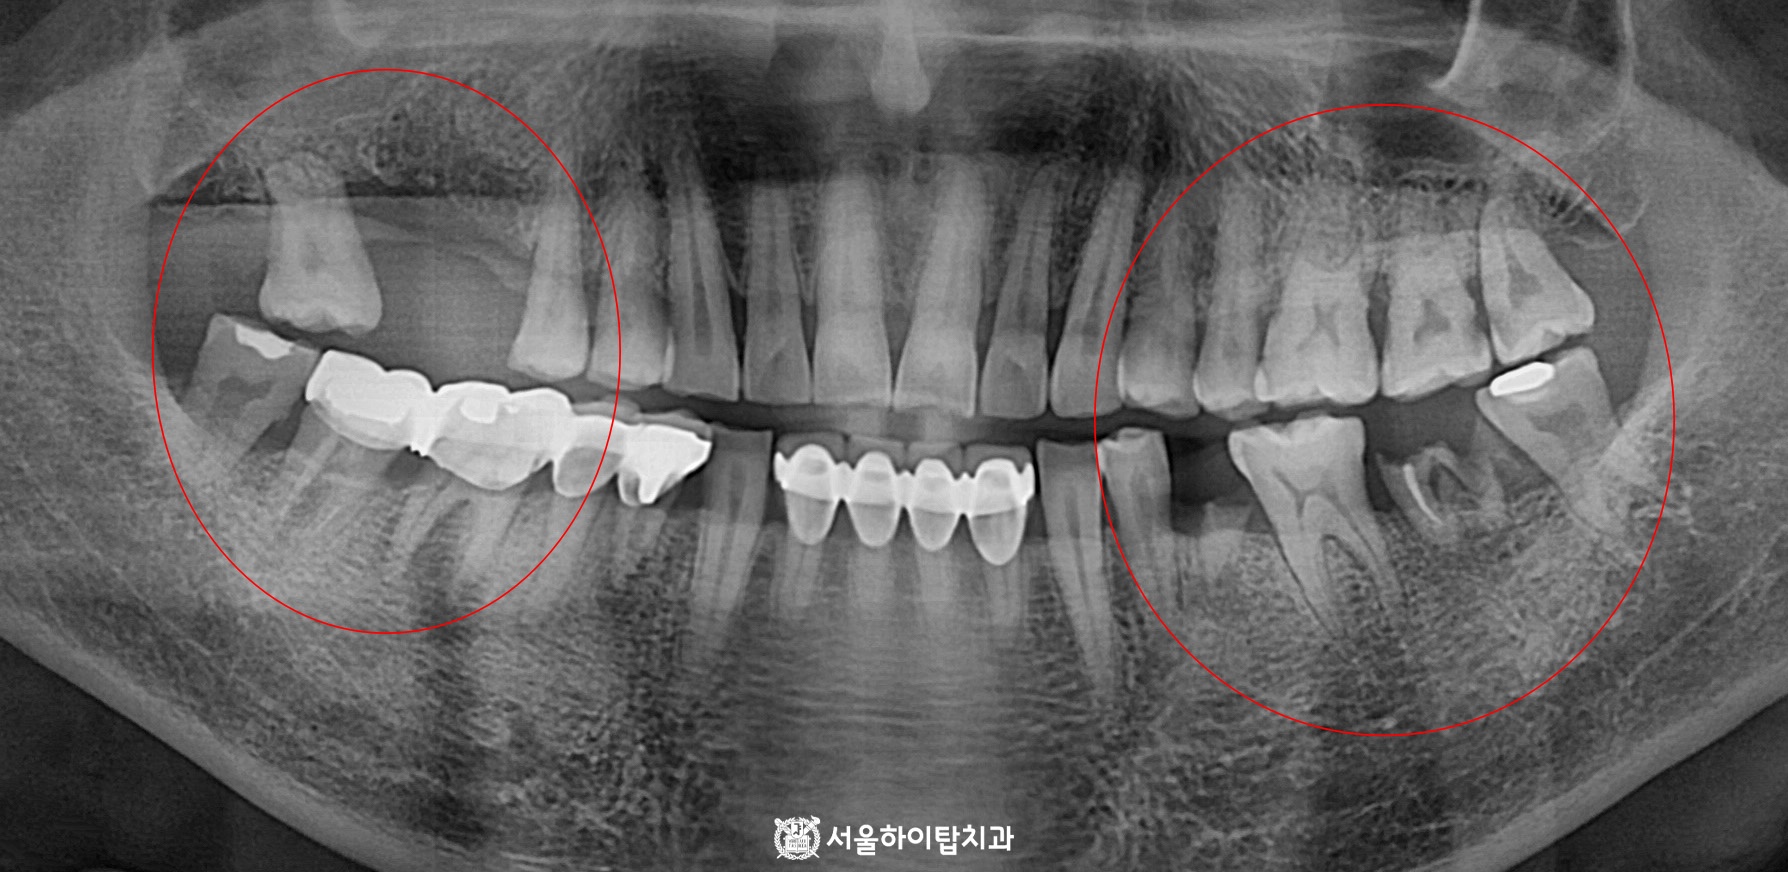

십정동 치과 상실된 치아가 불러오는 연쇄적 문제? 치조골 흡수와 기울어진 어금니, 뼈이식 동반 임플란트 과정 동암역 치과 : 균형 잡힌 저작이 중요한 이유, 전반적으로 손상된 치아 및 잇몸 임플란트를 통해 저작 기능 개선 간석역 치과 치주염으로 인한 치조골 흡수, 치아 파절 및 마모까지 임플란트 가상 시뮬레이션을 통한 안전한 수술 과정 1 2 Next Archives 2026년 4월 2026년 3월 2026년 2월 2026년 1월 2025년 12월 2025년 11월 Categories 미분류 신경치료 심미 치료 임플란트